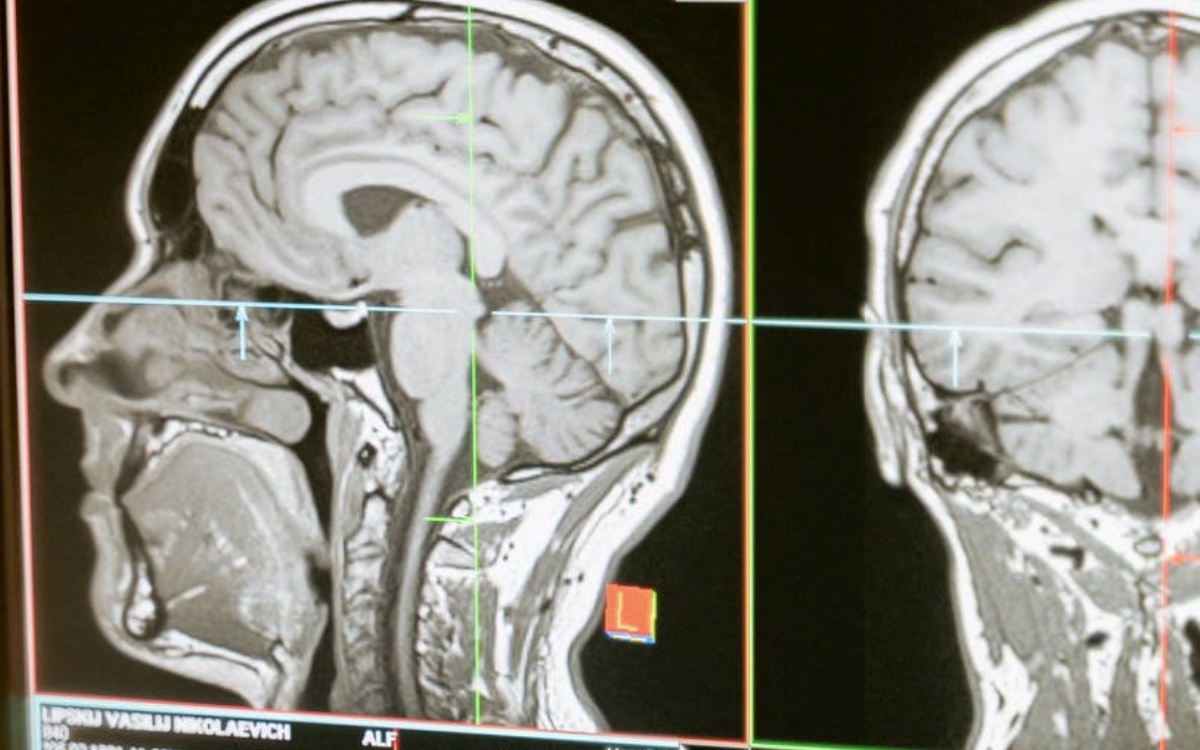

A volte è lo stress a procurarcelo, talvolta la mancanza di un riposo notturno adeguato e ristoratore. In alcuni casi però, è bene sapere che il mal di testa ha origini molto più serie e non dev’essere trascurato, come quando segnala la presenza di un’aneurisma.

in questi 4 casi infatti il mal di testa potrebbe essere avvisaglia di ictus, emorragia cerebrale e aneurisma, situazioni che, per evitare il rischio di morte o lesioni cerebrali, richiedono l’immediata somministrazione di farmaci e intervento medico.